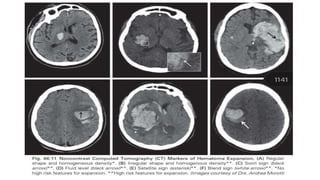

SPOT SIGN

• Spot sign: foci of enhancement

seen within the hematoma on CTA.

• Clinical implication:

Identification of contrast

extravasation and the spot sign are

potent and independent predictors of

hematoma expansion

SPOT SIGN ON CTA BRAIN